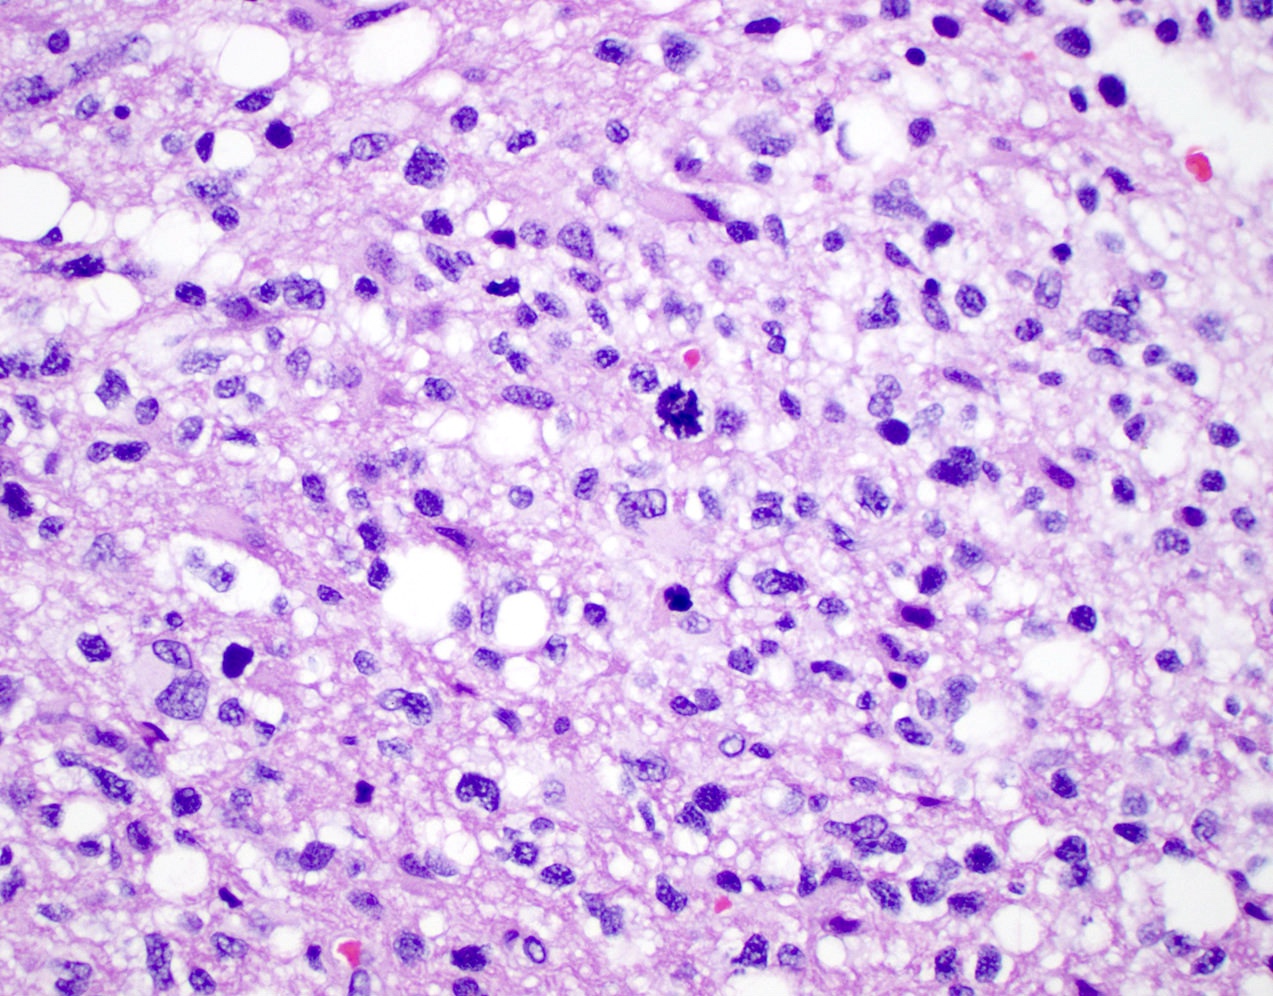

Microscopic (histologic) description

- Diffusely infiltrating tumor cells with oval to elongated astrocytic nuclei and varying appearance of tumor cytoplasm and fibrillar glial processes (Acta Neuropathol 2015;129:789)

- At the periphery, tumor cells may infiltrate in a diffuse single cell pattern, often with entrapped neurons and axons

- Cellular morphology is variable, even within a single tumor

- Commonly there is a mix of cells with elongated nuclei and fine fibrillar processes, cells with eccentric nuclei and glassy eosinophilic cytoplasm (gemistocytes), larger pleomorphic cells and small cells with scant cytoplasm

- May show oligodendroglioma-like areas

- Myxoid background and microcyst formation may be present

- Variable mitotic activity, cellularity and nuclear atypia depending on CNS WHO grade

- In small biopsy specimens, the presence of 1 mitosis may be sufficient for a CNS WHO grade 3 diagnosis, while the presence of a few mitotic figures in a large resection would not be sufficient for grade 3 designation (Acta Neuropathol 2020;139:603)

- Presence of necrosis or microvascular proliferation would be consistent with a CNS WHO grade 4 designation

Microscopic (histologic) images

Contributed by Eman Abdelzaher, M.D., Ph.D., John DeWitt, M.D., Ph.D. and Meaghan Morris, M.D., Ph.D.